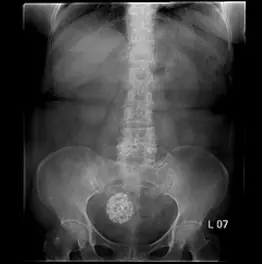

65歲女性病人因腹痛接受腹部X光檢查如附圖。最可能之診斷為何?

- 檢查項目:腹部 X 光 (KUB)。

- 影像特徵:在骨盆腔中央偏右側,可見一個邊界清楚的圓形腫塊影。

- 關鍵發現:該腫塊內部充滿了粗糙、斑駁、結節狀的鈣化點 (coarse, mottled calcifications),呈現典型的「爆米花狀 (popcorn-like)」外觀。

- 解剖位置:位於真骨盆腔內,恥骨聯合上方,符合子宮或卵巢的位置。

- 背景判讀:病人為 65 歲女性(停經後),骨盆腔內出現此類鈣化通常代表陳舊性的病變或良性腫瘤的變性。

本題影像展示了典型的鈣化性子宮肌瘤 (Calcified Uterine Leiomyoma)。 65 歲女性病人,腹部 X 光顯示骨盆腔有一顆邊界清晰、內部呈現粗糙「爆米花狀」鈣化的腫塊。這是子宮肌瘤經歷玻璃樣變性 (hyaline degeneration) 後,進一步發生鈣化變性的經典影像學表現。此徵象在臨床上具有高度特異性,幾乎可以直接診斷為陳舊性/鈣化的子宮肌瘤,無需考慮惡性腫瘤(如卵巢癌或子宮頸癌,其鈣化型態完全不同)。因此,最可能的診斷為 A。